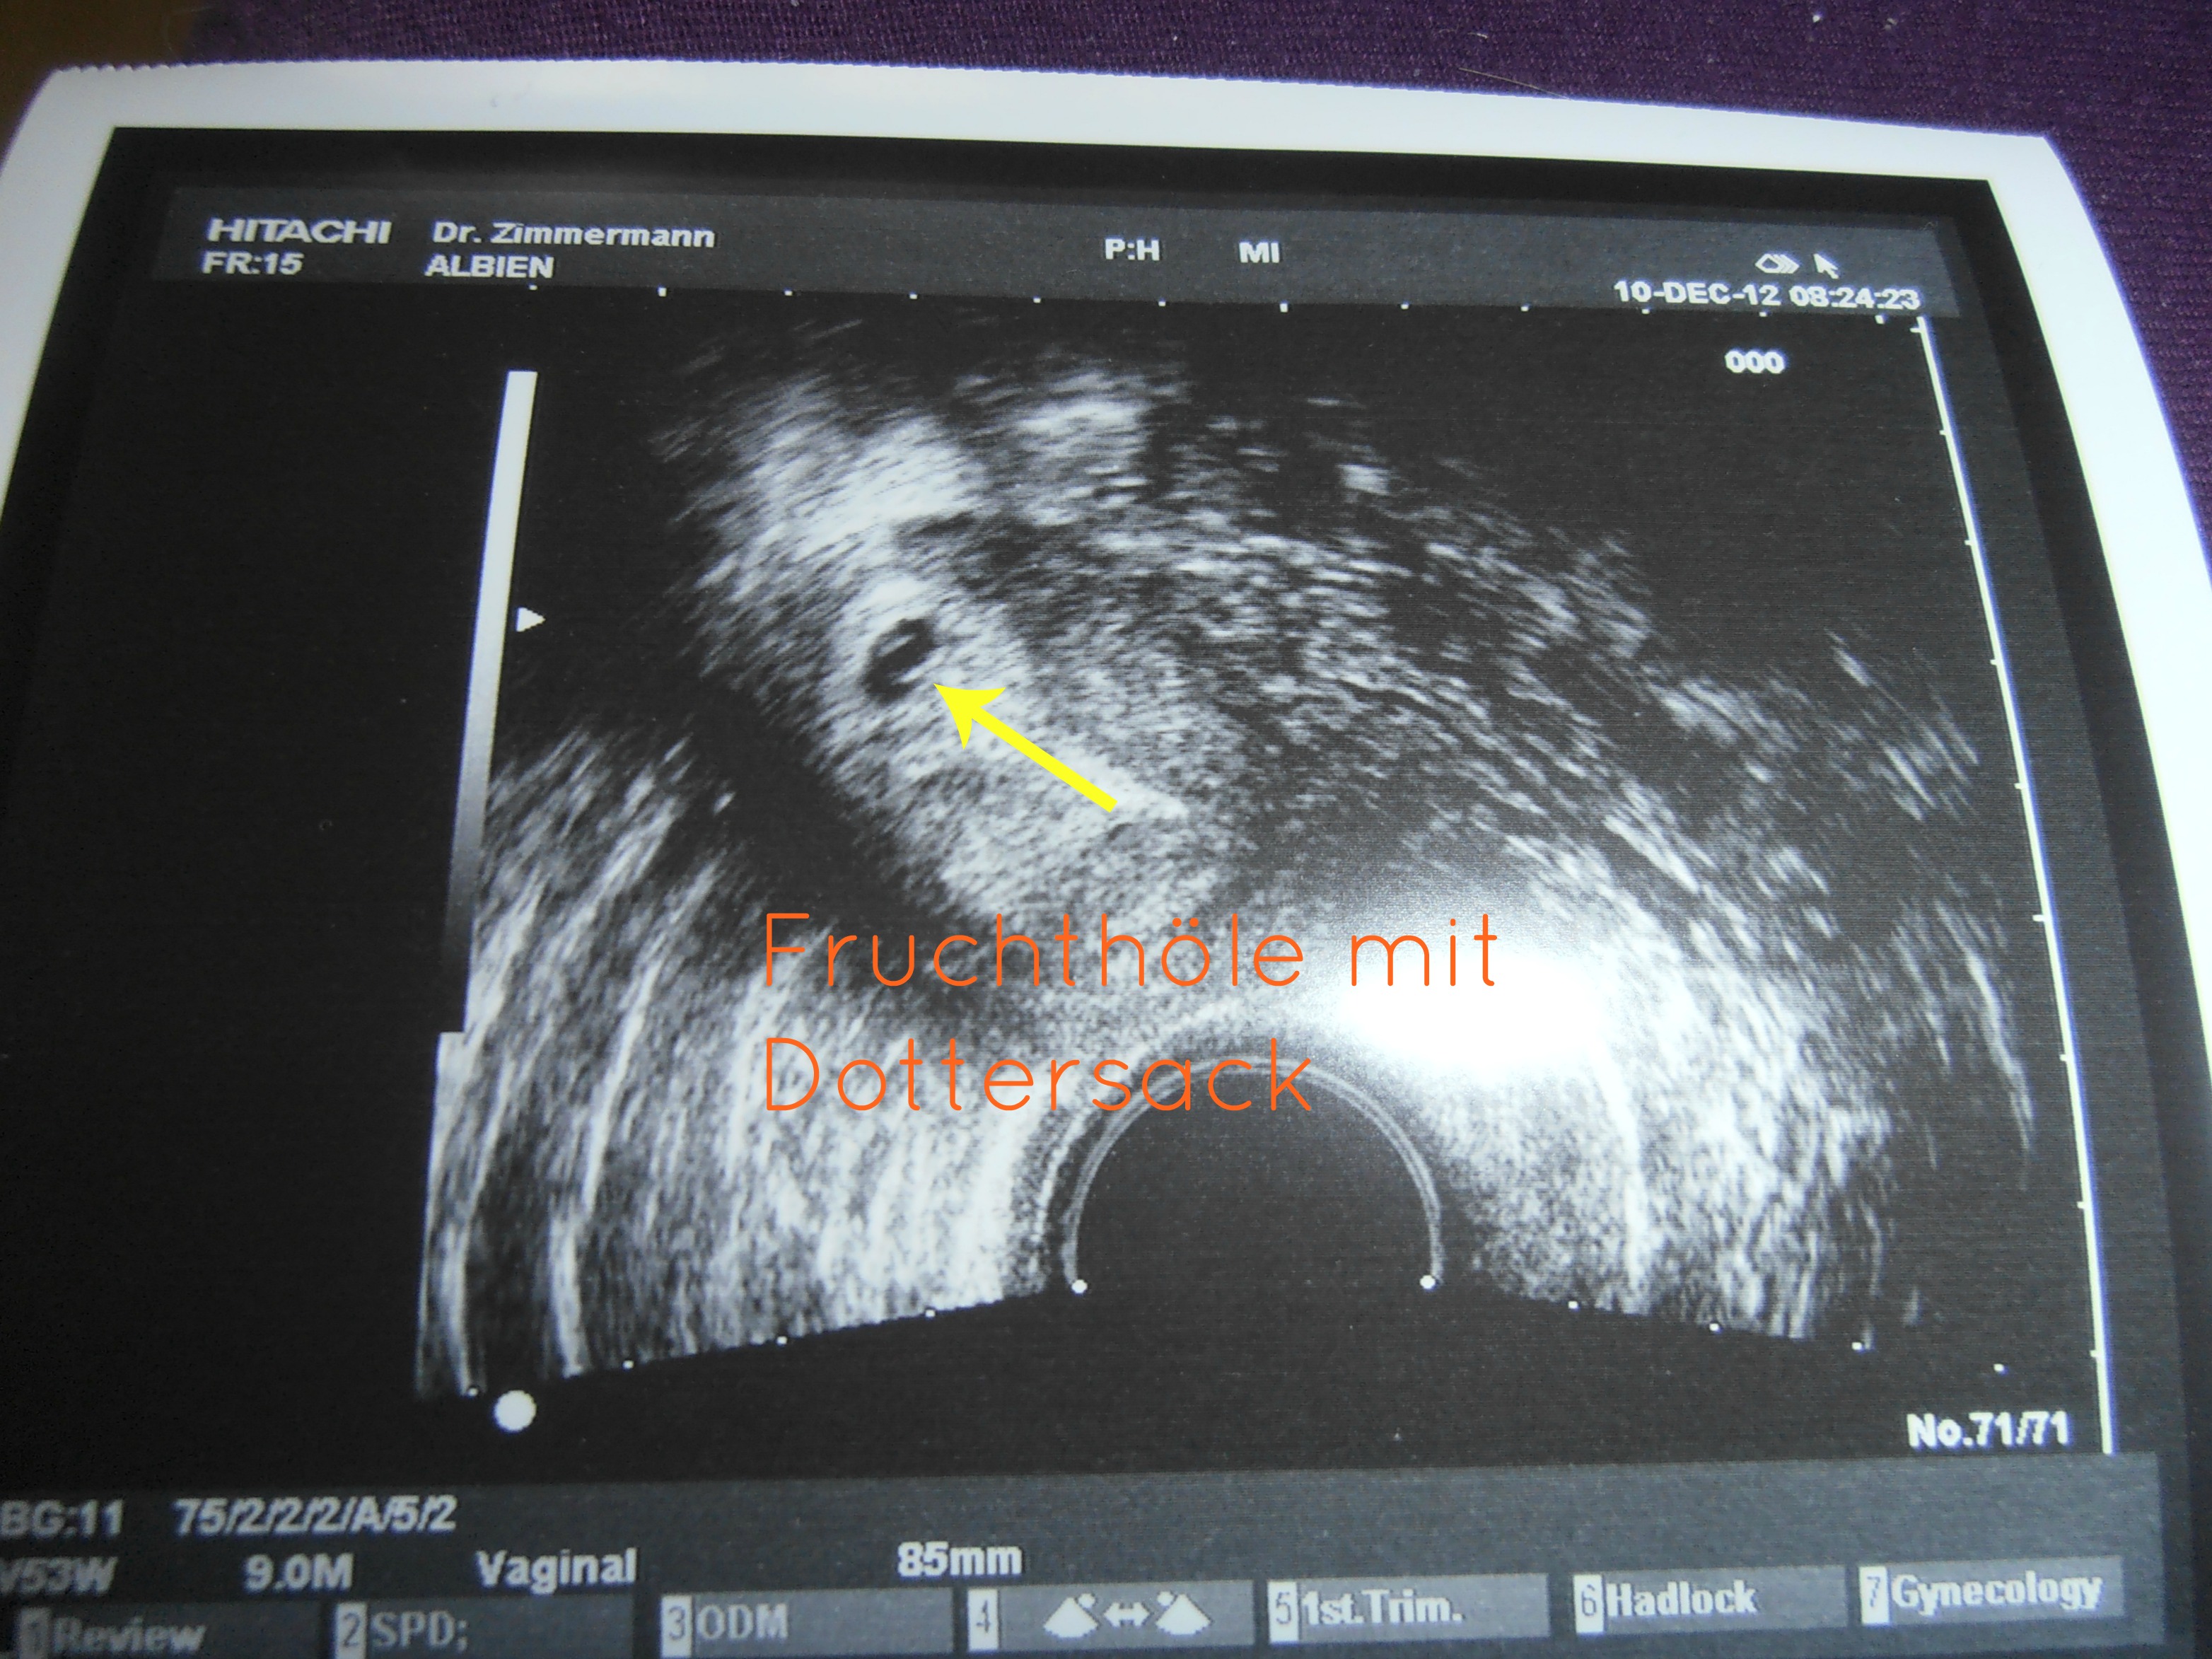

So ich war jetzt beim FA um mich anzapfen zu lassen . Die Ergebnisse bekomme ich heute Abend . Ich hab auch schon ein Ultraschallbild  , da ist allerdings nur die Fruchthöle und mit viel Fantasie der dottersack zu sehen . Ich liege viel im Bett da ich dauerblutungen seit Samstag habe.

also mein FA meint er hat eine Fruchhöle entdeckt . um klarheit zu schaffen hat er mir heute blut abgenommen und Montag noch mal hin um Blut abzugen (schaun ob sich der hCG wert angestigen ist) und auch ultraschall wird noch mal gemacht .